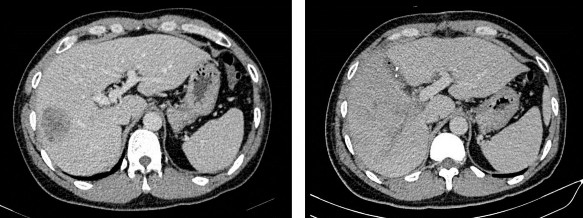

Hình 2.5. Gan trái trước (21/03/2019) và sau ALPPS thì một (09/04/2019) (BN N19-0079221)

2.6.3 Mức độ xơ gan trên giải phẫu bệnh

Mức độ xơ gan trên giải phẫu bệnh được đánh giá dựa trên kết quả giải phẫu bệnh phần nhu mô gan lành (bên cạnh kết quả bản chất u gan) theo thang điểm Ishak [46]. Kết quả này đã được kiểm tra và xác nhận bởi cùng một Bác sĩ Giải phẫu bệnh